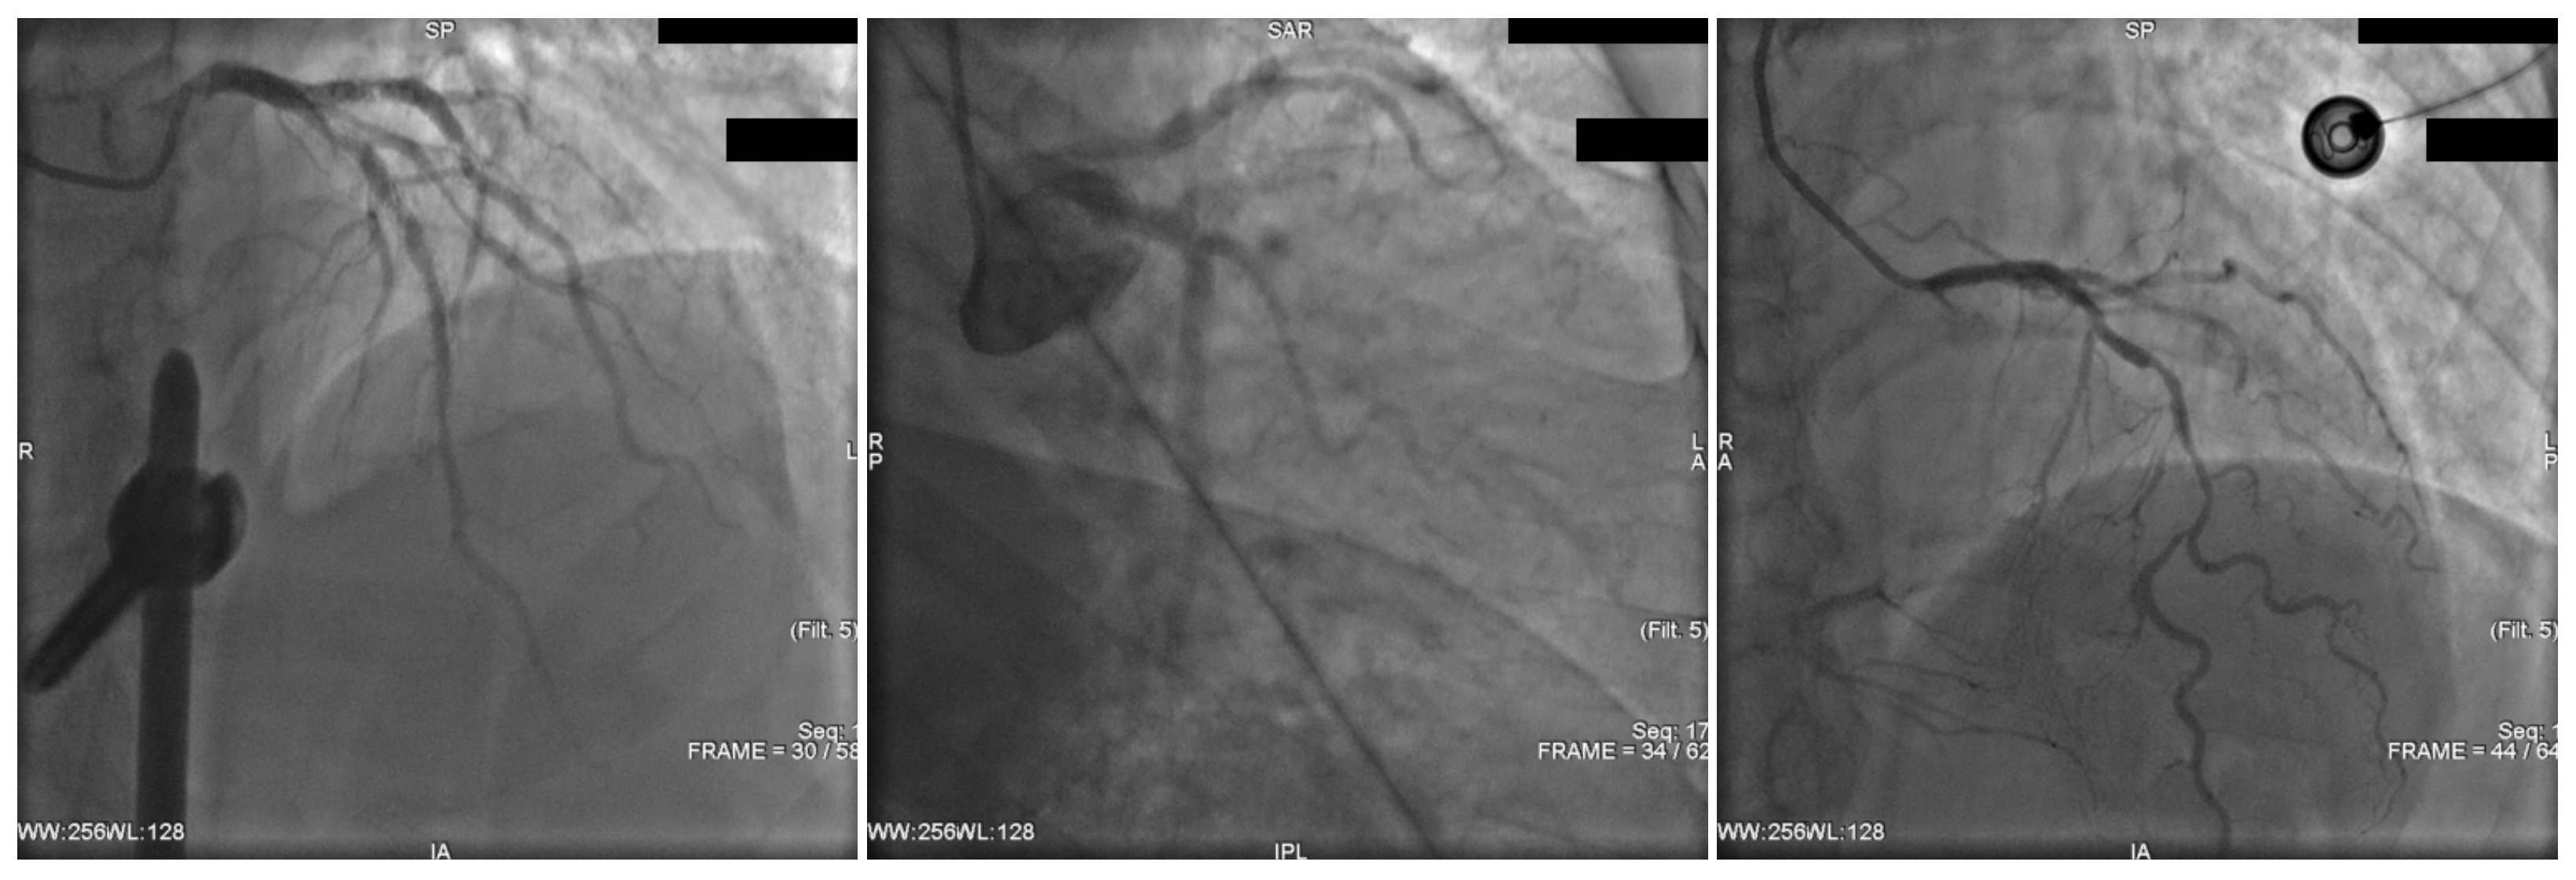

| View | Mean Score ± SD | ICC (2,1) | ICC (2,3) |

|---|---|---|---|

| LAO view for RCA | 4.48 ± 0.48 | 0.808 | 0.927 |

| AP caudal () | 4.18 ± 0.48 | 0.808 | 0.927 |

| LAO + CAU (spider view) | 4.22 ± 0.39 | 0.812 | 0.928 |

| RAO + CAU | 4.08 ± 0.51 | 0.827 | 0.935 |

| RCA cranial view | 4.52 ± 0.48 | 0.809 | 0.927 |

| RAO + CRA | 4.30 ± 0.47 | 0.803 | 0.925 |

| AP cranial () | 4.23 ± 0.47 | 0.806 | 0.926 |

| LAO + CRA | 3.92 ± 0.47 | 0.804 | 0.925 |

| Overall | 4.24 ± 0.49 | 0.828 | 0.935 |